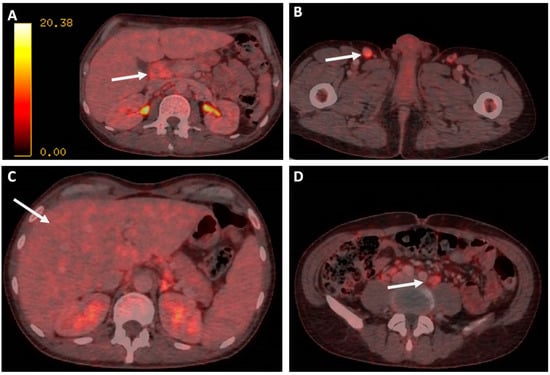

BM biopsy revealed isolated ample cytoplasmic cells with one or more nuclei with prominent nucleoli-expressing CD15, CD30, PAX5, and EBER as well as images of hemophagocytosis with hardly any residual normal hematopoietic tissue. Reed–Sternberg cells were observed. In addition, large numbers of polytypic plasma cells and a striking increase in CD3/CD8-positive small T lymphocytes and abundant loose epithelioid histiocytes were also shown, with no granuloma formation. These cells did not show expression for CD20 or CD79a. Furthermore, no human herpes virus 8 (HHV8) positive cells or an increase in the number of blasts were observed (Figure 1).

These findings make the diagnosis of Hodgkin’s lymphoma (HL) more likely.

Figure 1. Bone marrow biopsy. (A): Hematoxylin eosin stain × 40. (B): EBER in situ hybridization. (C): PAX5. (D): CD30.